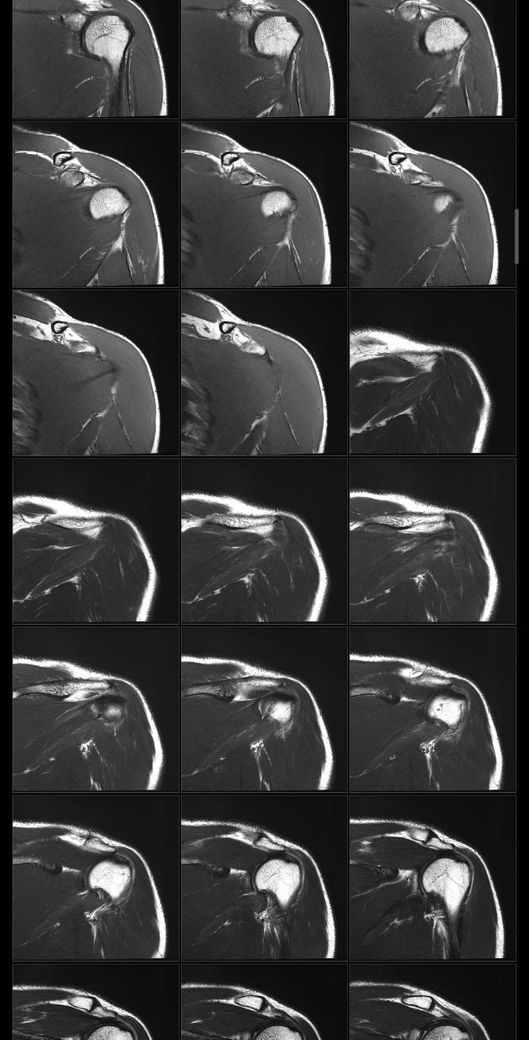

어깨 mri 전문의 소견 부탁드립니다

얼마전에 축구하다가 넘어지고 그날 저녁부터 팔이 안올라가서 건협가서 mri 찍었습니다.

회전근개 파열이 있는지, 없다면 지금 상태가 어떤상태인지와 웨이트 운동 가능할정도의 회복기간이 궁금합니다

• 1번 째 사진

• 2번 째 사진

• 3번 째 사진

• 4번 째 사진

Mri에서 별다른 이상소견이 없는 경우 일시적으로 발생하는 움직임이나 기능의 제한일 수 있습니다.

약 2주 이내의 회복기간이 소요될 수 있으며, 현재 mri 사진에서 보이는 염증 소견은 타박상으로 인해서 발생하는 것일 수 있습니다.

별다른 파열의 징후는 보이지 않습니다.